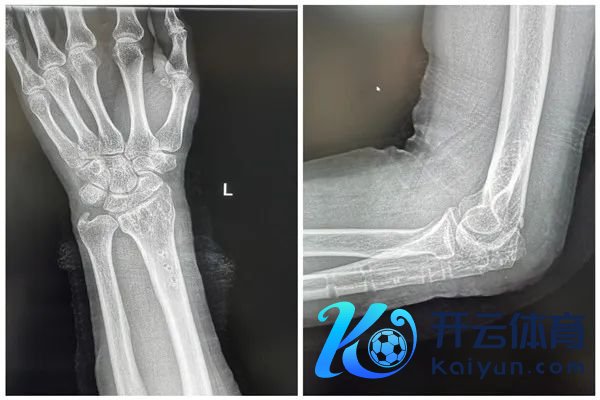

术前、术后X光

经过一年的不懈勤苦,何先生的康复效用令东说念主堤防。他的左上肢功能已基本收复,不仅不错自如地活动,还能胜任绝大部分平方家务服务和使命。这一权贵的跨越不仅让他深感欣忭,也让周围的东说念主对他的康复之路充满了敬佩与感触。